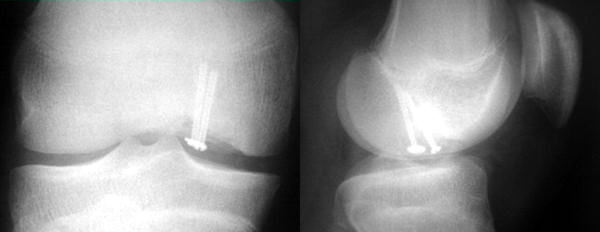

İnternal tespit için metal vidalar, biyobozunur implantlar, K-telleri, kortiko-kansellöz çubuklar gibi birçok farklı yöntem tarif edilmiştir. Stabil bir tespit için en az iki implant gerekir ancak parçanın boyutuna göre bu sayı artırılabilir. Tespit sonrasında 6-10 haftalık bir süre bacağa yük verilmesinden kaçınılmalıdır.